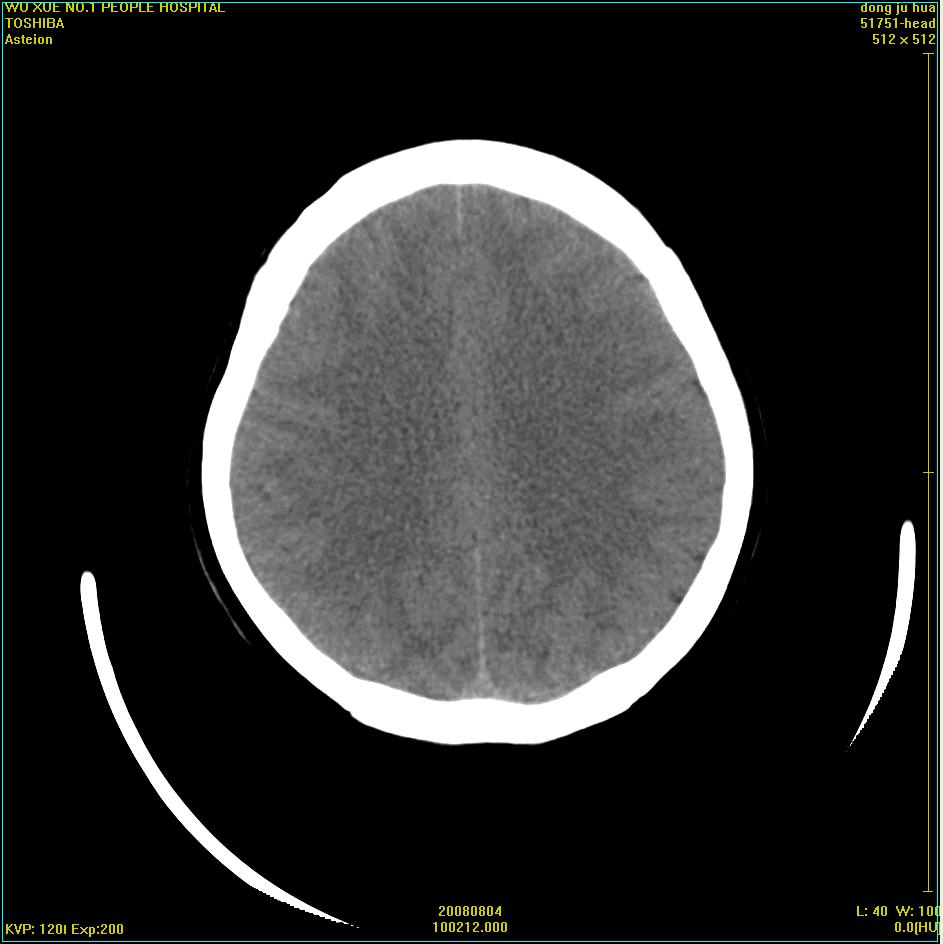

患者,女,45岁。四年前在我院做ct诊断为右侧桥小脑脚区三叉神经鞘膜瘤,已做手术。今复杳。请大家看看

三叉神经鞘膜瘤术后

看来复发了。建议mri检查。

考虑三叉神经鞘膜瘤术后复发并瘤体内出血。

三叉神经鞘膜瘤术后复发并瘤体内出血

考虑慢性扩张性血肿吧!请大家再看看,发表高见!

考虑:三叉神经鞘膜瘤术后复发并瘤体内出血。支持!

四年前做的手术,为什么大家不考虑慢性颅内血肿呢?

考虑慢性颅内血肿?症状体征有多少?能否发上?